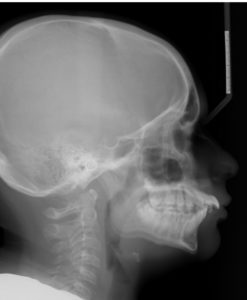

A 13.3 year old caucasian male presents with a chief complaint that “my upper teeth stick out”